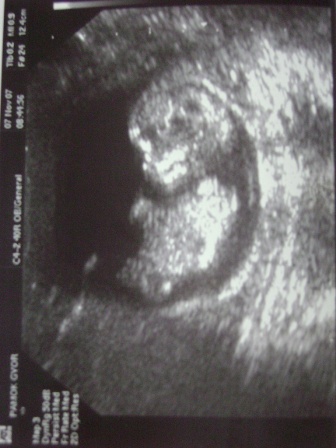

itt a képecske csöppecskéről :)

64 mm és nagyon sokat nőtt a multhéthez képest.

Nem tudom hogy a csoki hatása e de megsem állt..folyton mocorgott alig birták lemérni..először fejjel lefelé volt majd vízszintesbe ment és hátat fordított :lol: :lol: A dokinéni már ugy könyörgött neki hogy legyen jó és ne mozogjon és mutassa magát :)

Mindent rendben találtak :)